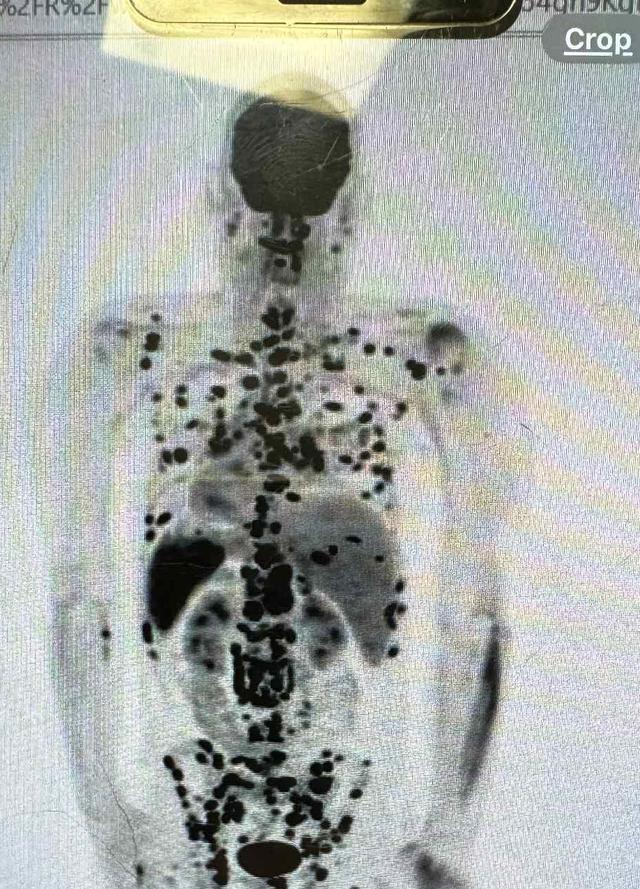

After a year of thinking his back, neck and arm pain was just a run of the mill injury not responding to standard treatment and rehabilitation - ultrasounds, MRI and blood tests have incidentally revealed innumerable bone lesions throughout Wills' skeletal system, indicating some form of bone/blood cancer.

After a long and challenging journey, we finally have a confirmed diagnosis: Sarcoidosis. While this condition typically affects the lungs, heart, and eyes, in my case it has taken a rare and aggressive form—primarily damaging my bones. Unfortunately, this has brought an end to my building career, as the physical demands and risks are no longer safe for me to manage.

Moving forward, pain management will be a long-term part of life, and the treatments for Sarcoidosis come with their own difficult side effects. Due to the delay in diagnosis and the progression of the disease, my long-term outlook remains uncertain.